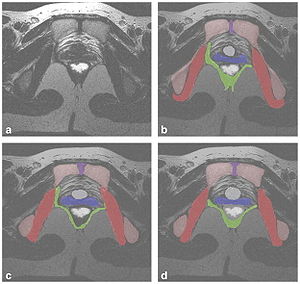

- 4.43 Evaluation of Prostate Segmentation Algorithms for MRI: The PROMISE12 Challenge